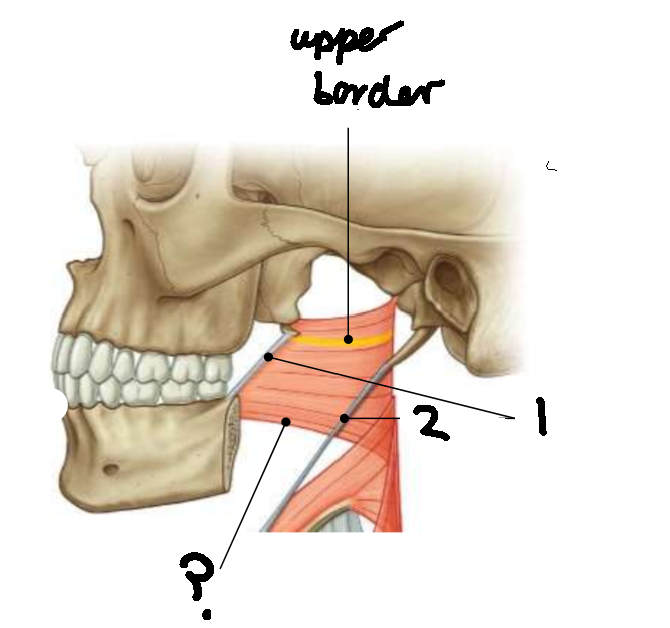

What muscle is this?

superior constrictor

What is the upper border of this muscle?

palatopharyngeal sphincter

What is 1?

pterygomandibular raphe

What is 2?

stylohyoid ligament

What are the attachments of this muscle?

pterygoid hamulus, pterygomandibular raphe, posterior end of mylohyoid line → pharyngeal raphe